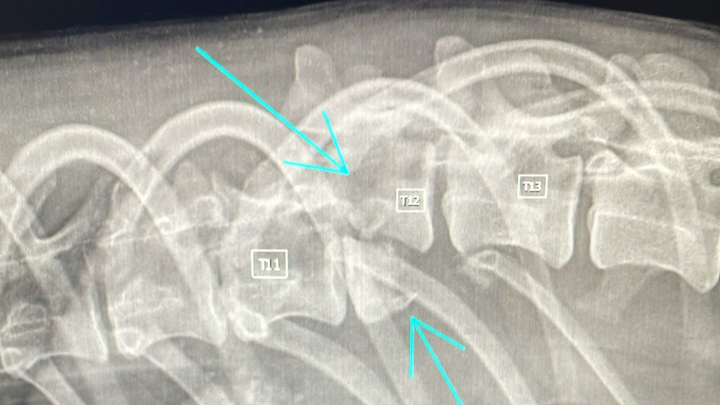

Come ho già scritto chappy ha Una lussazione di colonna, ciò significa che potrà condurre una vita da cane paraplegico a vita e che non tornerà a camminare con le sue zampe ad eccezione di un tentativo di sviluppo di andatura spinale ma non c'è certezza che questo avvenga.

Tecnicamente dopo intervento di stabilizzazione colonna vertebrale+ lunga fisioterapia in acqua si potrebbe verificare la possibilità di andatura spinale o nella peggiore delle ipotesi carrellino a vita.

Ad oggi non c'è certezza sul fatto che potrà avere un recupero e prima di finire in sala chirurgica con un intervento sarebbe opportuno effettuare una Tac da lì decidere di operare o eutanasia.